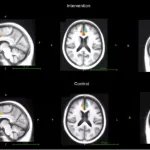

In positron electron tomography, only BrainHQ cognitive training participants showed improvements in cholinergic activity: in the anterior cingulate cortex, the main region of interest, and in memory-related areas, the hippocampus and parahippocampal gyrus. At the same time, the reaction speed on tests increased, and this effect persisted three months after the end of training.

Фото: JMIR Serious Games

Changes in the anterior cingulate cortex at post-test compared to baseline, averaged across training (top) and control (bottom) participants.